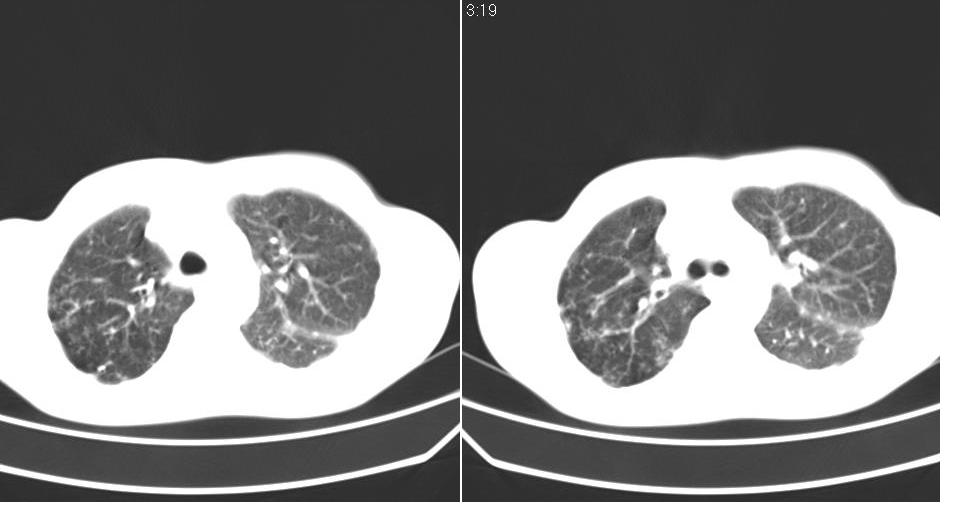

以下是引用苯小孩在2007-6-27 15:09:00的发言:[br]考虑:1、右肺继发性肺结核.2、双侧包裹性积液<胸腔及叶间>3、双侧局部胸膜增厚.[br]建议胸水化验检查.

以下是引用yanghaochen88在2007-6-27 15:08:00的发言:[br]双肺上野散在粟粒状影、包裹性积液、胸膜增厚粘连、叶间积液---tb,至于分型还得结合病史体征细究妥当些。